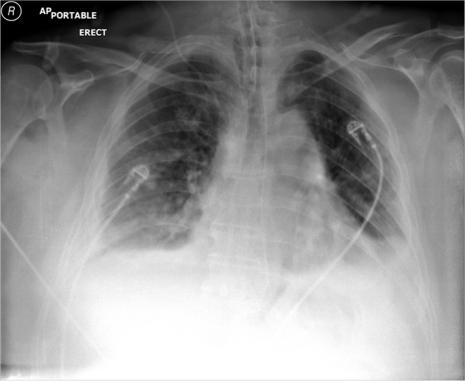

Lung herniation is a relatively rare clinical entity that is most commonly either congenital or acquired traumatically. We describe a case of spontaneous lung herniation secondary to acute cough in an obese male smoker complicated by contralateral acute lung injury and systemic inflammatory response syndrome (SIRS). Mechanisms of lung herniation, classification, diagnosis, and management will be discussed.

https://cdn.ncbi.nlm.nih.gov/pmc/blobs/8c7c/3201100/bb25f0eb7278/ccrep-4-2011-039f1.jpg